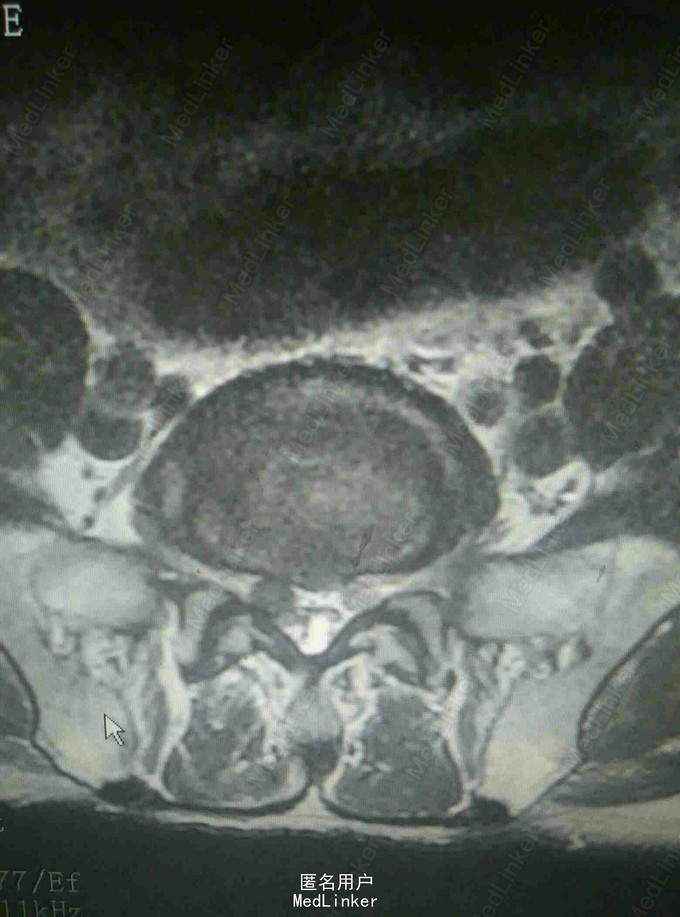

查体:腰4~5棘突及骶部压痛,无明显叩击痛,右大腿外侧疼痛,右足背外侧感觉减退,双下肢肌力正常,双侧直腿抬高实验阴性。 辅查:外院X线片提示腰椎退变 我院核磁提示腰4-5关节突增生内聚,椎间盘后突压迫硬膜囊及神经根

诊断:腰椎管狭窄 治疗:腰椎后路减压植骨内固定术